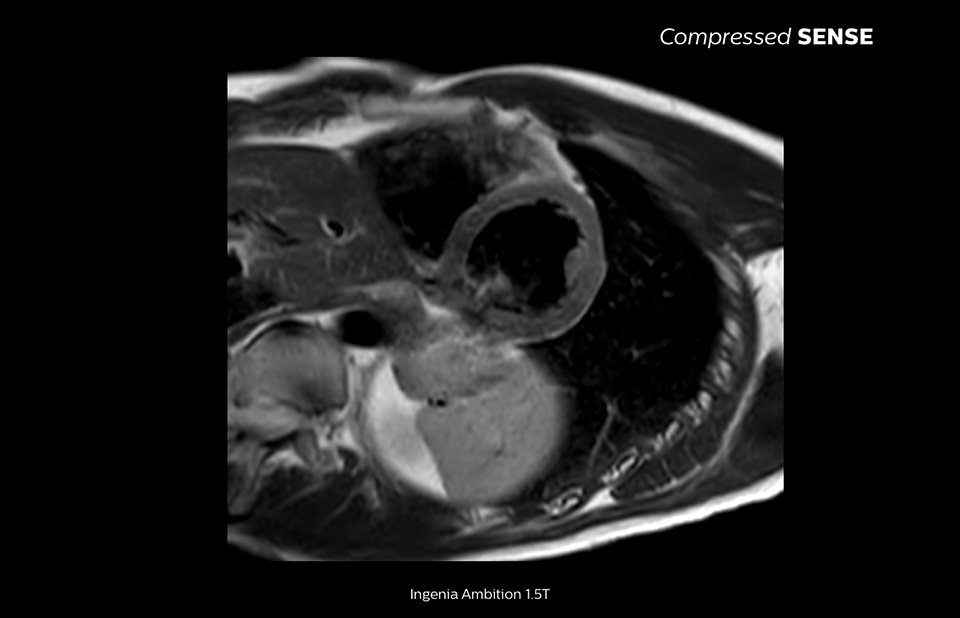

The MRI staff at Kurashiki Central Hospital incorporated Compressed SENSE into most of the brain, spine, abdominal, and cardiac examination protocols on their Ingenia 1.5T, resulting in fast and high-quality MRI scans, which is welcomed by patients and staff.